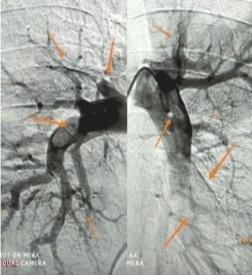

术中造影可见双肺多发栓塞

接诊的周围血管科医生冯云霞检查后怀疑是下肢急性深静脉血栓,不排除肺栓塞的可能。很快,黄先生的血压降至84/57毫米汞柱,肺动脉CT血管造影显示:双肺多处动脉栓塞。经过紧急手术治疗,黄先生转危为安。